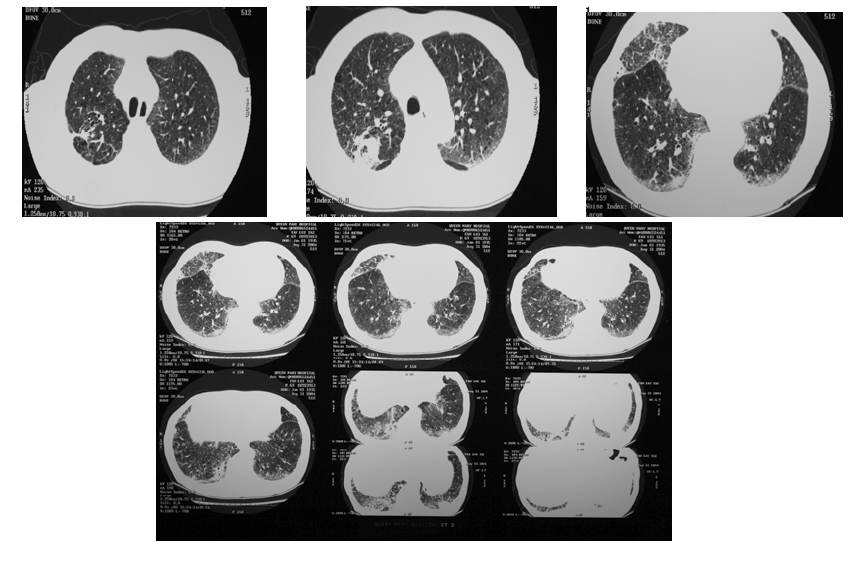

CT thorax was done in 8/2004 (Fig. 2a and 2b) and showed:

1. Mild emphysema

2. Multiple enlarged mediastinal, hilar, axillary, mesenteric and para-aortic lymphadenopathy

3. Focal subpleural contrast enhanced consolidation in RUL posterior segment and bilateral lung bases

4. RML and subpleural groundglass with traction bronchiectasis